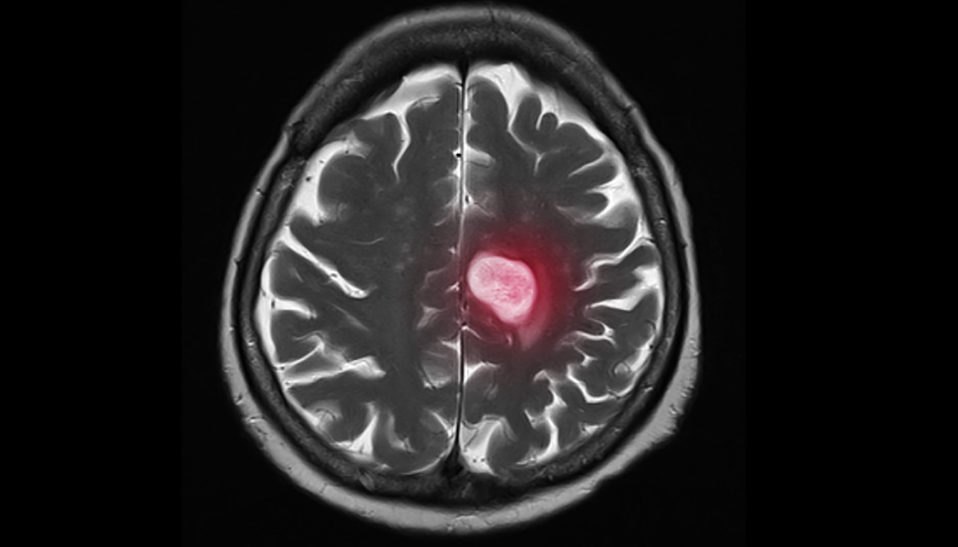

Brain Cancer

A Closer Look at Glioblastoma and New Reasons for Hope

The World’s First Oncolytic Virus Drug was Launched to Treat Malignant Brain Tumor GBM